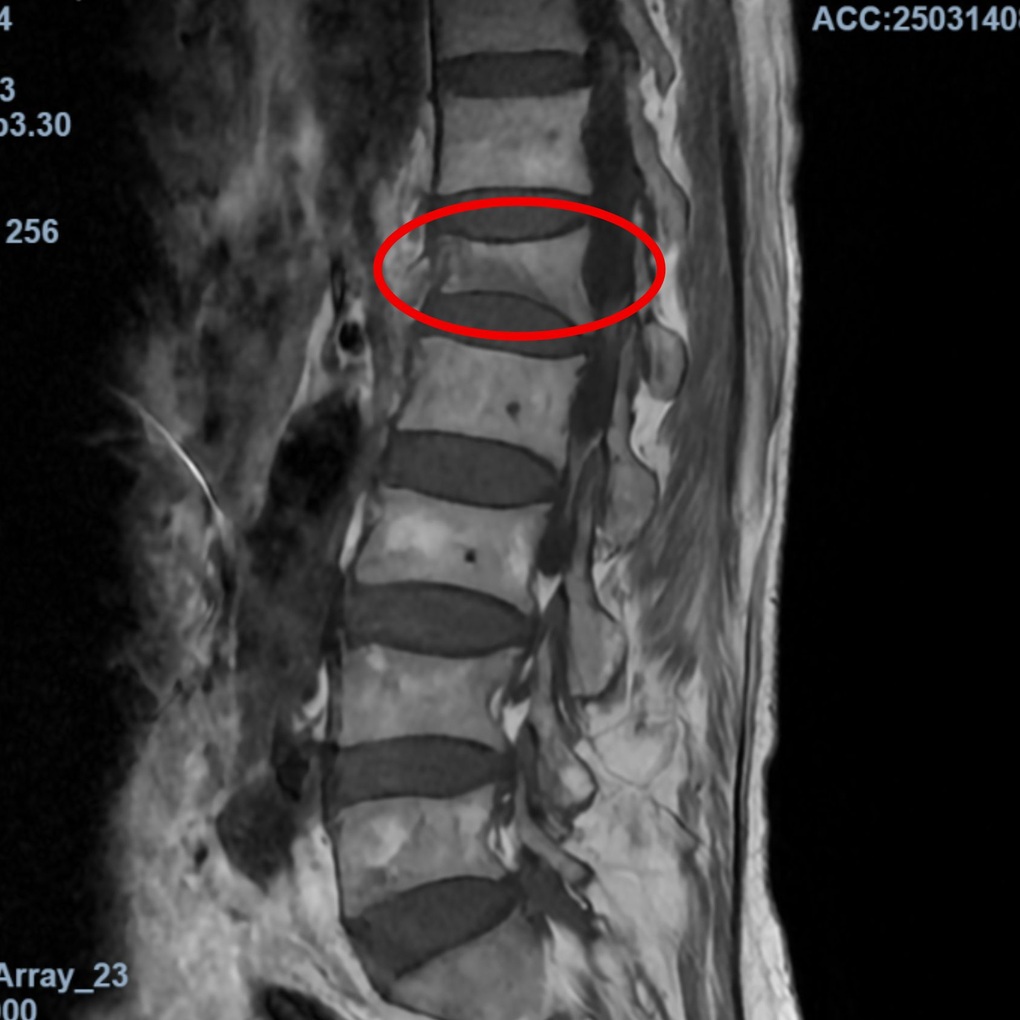

Phim chụp MRI đốt sống L1 bị xẹp khiến bệnh nhân đau lưng, mất vận động (Ảnh: BVCC).

Qua khai thác bệnh sử và chẩn đoán trên phim chụp MRI, TS.BS Trịnh Tú Tâm, Trưởng khoa Chẩn đoán hình ảnh và Điện quang can thiệp BVĐK Hồng Ngọc – Phúc Trường Minh cho biết: “Bệnh nhân lớn tuổi, kết hợp tiền sử mắc Lupus ban đỏ mạn tính phải sử dụng thuốc điều trị trong nhiều năm khiến mật độ xương giảm mạnh, dẫn tới tình trạng loãng xương nặng, mất vững cấu trúc cột sống. Do đó, chỉ 1 động tác kéo tay nhẹ của cháu bé cũng khiến đốt sống bị lún xẹp”.